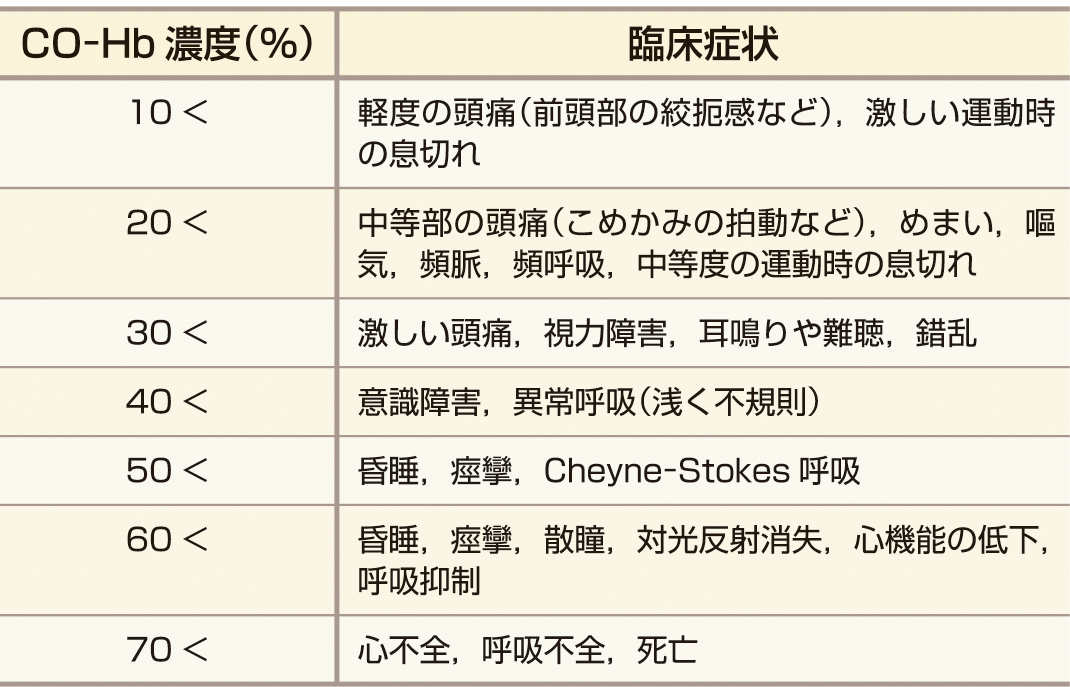

i) 急性期: エネルギー代謝速度の大きい中枢神経系と心臓の症状が中心となる.表1にCO–Hb濃度と臨床症状を示すが,必ずしもこのように相関しないことに注意が必要である.

ⅲ) MRIおよびCT (急性期): 急性期には両側の淡蒼球にMRIでは異常信号が,CTでは低吸収域がみられることがある (図1).その他にMRIではレンズ核 (淡蒼球および被殻 (ひかく)) ・淡蒼球以外の基底核 (被殻,尾状核,視床) ・脳室周囲または皮質下の大脳白質・大脳皮質・海馬・小脳などの異常信号や,脳浮腫が認められることもある.